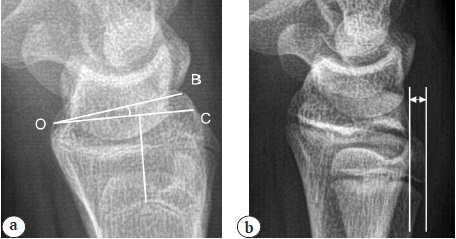

- The radioulnar angle (inclination of the radius in the frontal plane) is formed by two intersecting lines, namely, a line perpendicular to the long axis of the radius and a line drawn from the top of the radial styloid process to the ulnar edge of the articular surface of the radius, which were measured on images in frontal view (Fig. 2). According to the literature, the value varies from 13° to 30° and averages 22–24° [17]. The spread of values is largely due to the choice for measuring the surfaces of the radius (dorsal or palmar).

Fig. 2. X-ray of the wrist joint in direct projection. The radioulnar angle (∠AOB) is formed by line BO, perpendicular to the long axis of the radius, and line AO, drawn from the apex of the styloid process of the radius to the ulnar edge of the articular surface of the radius

- The volar angle (inclination of the radius in the sagittal plane) is measured on lateral radiographs. This angle is formed by two lines, namely, a line perpendicular to the long axis of the radius and a line drawn between the two edges (dorsal and palmar) of the articular surface of the radius (Fig. 3 a). According to the literature, this indicator is normally 10–12° [3, 18].

Fig. 3. X-ray of the wrist joint in lateral projection: a — volar angle (∠BOC) formed by line CO, perpendicular to the long axis of the radius, and line BO, connecting the two edges (dorsal and volar) of the articular surface of the radius; b — radioulnar distance between the dorsal contours of the epiphyses of the radius and ulna

- The radioulnar distance is the distance between the dorsal contours of the epiphyzes of the radius and ulna on radiographs in the lateral view. It is measured in millimeters; according to the literature, it averages −2 to +17 mm in the adult population [19]. A negative radioulnar distance value indicates that the ulna is located dorsal to the radius (Fig. 3 b).